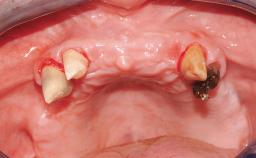

Transition from an “irrational to treat” Maxillary Dentition to a Full-Arch Segmented FDP by Early Loading of Eight Implants Placed Using the Staged Approach

The staged approach permits the transition from an “irrational to treat”dentition to a full arch implant supported restoration without any need to use a removable provisional prosthesis or to apply the immediate-placement and immediate-loading techniques.  A failing dentition is the usual indication for a staged treatment. On the other hand, the dentition should still contain many residual teeth, but with few or none of them being suitable for use as definitive abutments for a full-arch fixed restoration.This situation is usually the result of advanced periodontal disease or of the failure of an extensive fixed prosthesis.